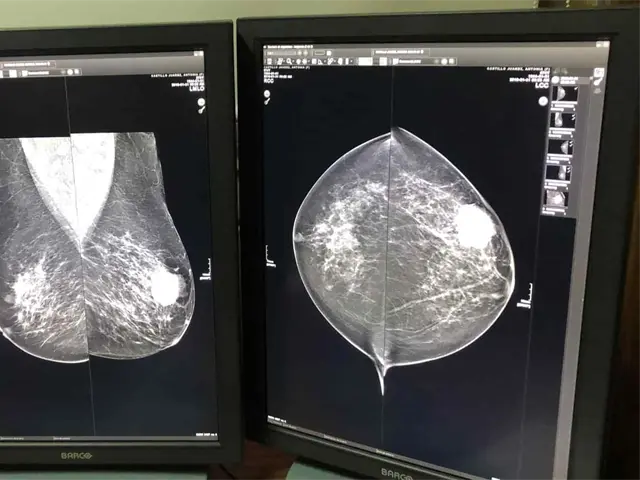

Alertó sobre la importancia de la detección temprana del cáncer de mama y expuso que la sobrevida de una paciente detectada en estadio uno es hasta de 95 por ciento, mientras que cuando se diagnostica en estadio cuatro la situación cambia drásticamente al ser la sobrevida a cinco años de tan sólo el siete por ciento.

La educadora certificada en diabetes recomendó llevar una vida saludable, practicar la autoexploración mensual desde los 20 años de edad, realizarse exámenes clínicos anuales a partir de los 25 años y recurrir a las mastografías a partir de los 40.